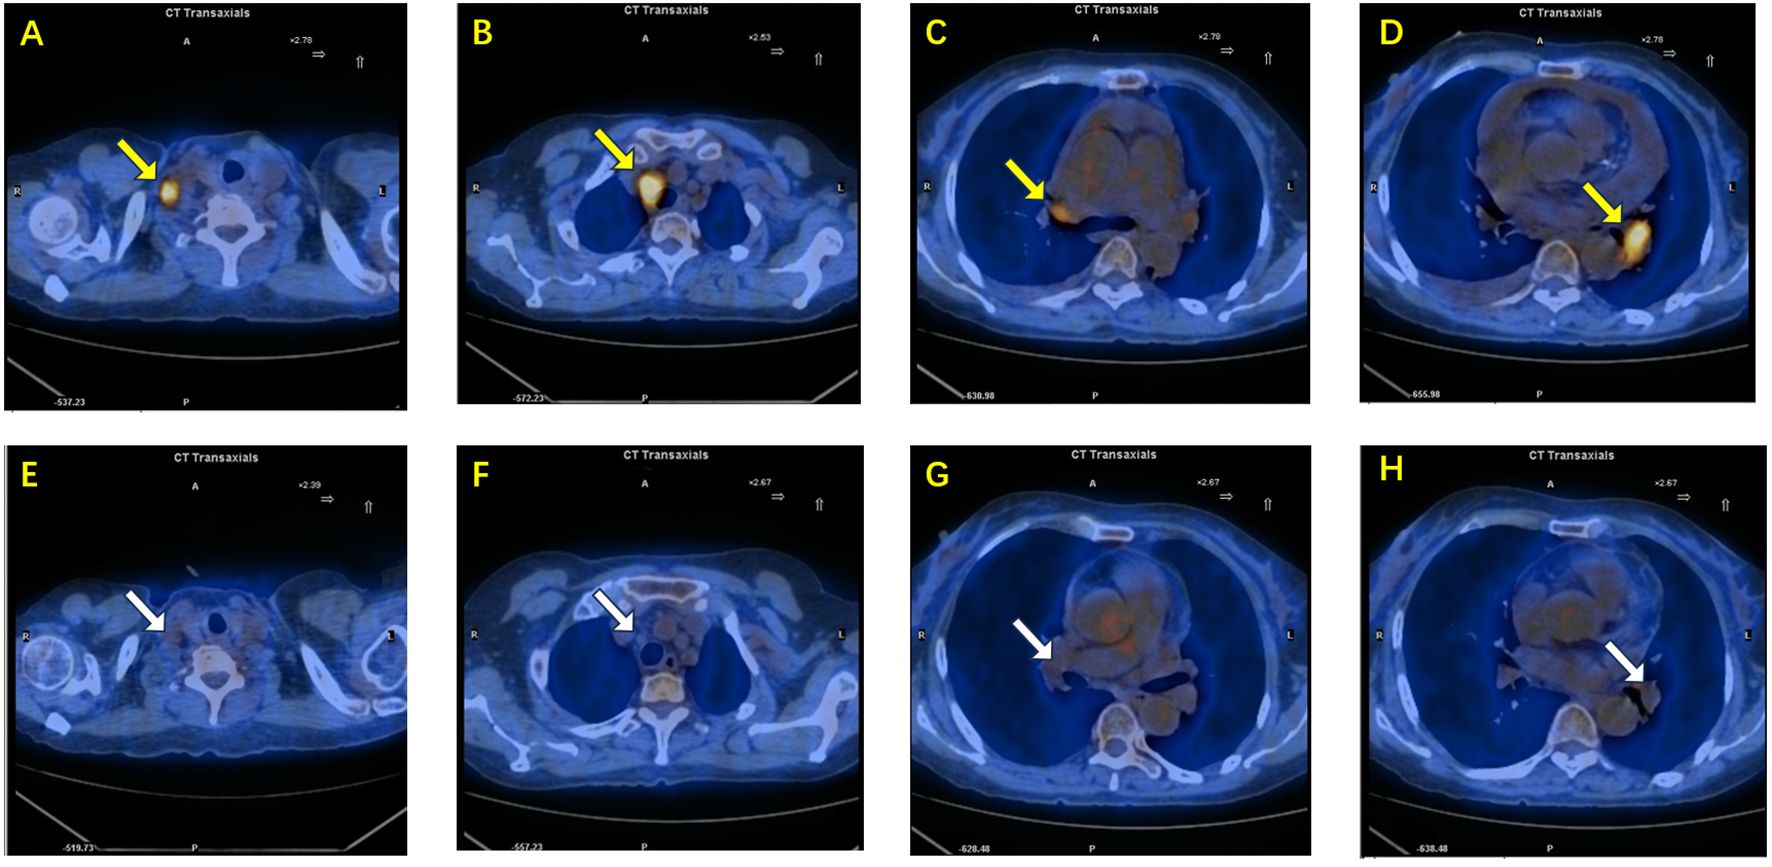

BRAF V600E mutation defines a rare but targetable subset of NSCLC. We report a 70-year-old non-smoking woman with unknown primary lung adenocarcinoma presenting with multistation mediastinal lymph-node metastases and massive malignant pleural and pericardial effusions. Molecular profiling showed BRAF V600E mutation and high PD-L1 expression(TPS 90%, CPS 95). The patient received combined dabrafenib, trametinib, and pembrolizumab with close safety monitoring, achieving rapid tumor control and complete remission by six months with manageable toxicity. This case suggests that early integration of PD-1 blockade with BRAF/MEK inhibition treatment may benefit selected patients and underscores the value of comprehensive molecular and immunohistochemical assessment to guide individualized therapy.